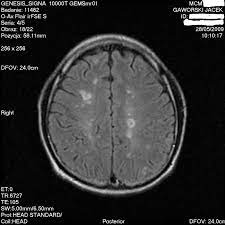

Rezonans magnetyczny pozwala na wykrycie nawet najmniejszych blaszek (płytek) i umożliwia ich odróżnienie od zmian spowodowanych obecnością guza lub uszkodzeniem naczyń krwionośnych, na przykład w wyniku urazu. Że pacjent choruje na stwardnienie rozsiane. U nas, chorych na sm, metoda ta potwierdza obecność ognisk demielinizacji, charakterystycznych dla stwardnienia rozsianego. Przy współpracy z awf wrocław, zapraszamy chorych na stwardnienie rozsiane (sm) oraz osoby po udarze mózgu na cykl zabiegów z wykorzystaniem rezonansu stochastycznego (srt). Głównym badaniem obrazowym, pozwalającym na wykrycie sm, jest rezonans magnetyczny głowy, mózgu oraz rdzenia kręgowego. Stwardnienie rozsiane (sm) a ciąża diagnostyka sm: Tak , podobno stwierdzono , że hormon produkowany na początku ciąży , może być wykorzystany w terapii sm.nawet zaczęto pracować nad stworzeniem leku opratego o ten hormon.ale jeśli wszystko się uda , to będzie on dostępny za dobre parę lat. Badanie jest w zupełności bezpieczne.

Badanie jest w zupełności bezpieczne. Sclerosis multiplex, sm) jest przewlekłą, autoimmunologiczną chorobą ośrodkowego układu nerwowego.objawia się stopniową degradacją osłonek mielinowych włókien nerwowych, co utrudnia przesyłanie impulsów pomiędzy nerwami. Czasami konieczne jest wykonanie punkcji lędźwiowej. Dwa jasne ogniska po lewej stronie odpowiadają obszarom demielinizacji p.grieb, l.królicki, wpaść w rezonans stwardnienie rozsiane jest jedną z najczęstszych przewlekłych i nieuleczalnych chorób neurologicznych, która na ogół diagnozowana jest między 20. Na stwardnienie rozsiane chorują ludzie do 50 roku życia, potem ryzyko zachorowalności spada. Rezonans magnetyczny głowy oraz kręgosłupa; Na podstawie przedstawionych przez panią danych tj. Diagnoza stwardnienia rozsianego rezonans magnetyczny. Przebieg choroby różni się u każdego człowieka, ale u większości występują okresy zaostrzenia choroby a potem następuje poprawa. U nas, chorych na sm, metoda ta potwierdza obecność ognisk demielinizacji, charakterystycznych dla stwardnienia rozsianego. Stwardnienie rozsiane uznawane jest za najczęstszy czynnik neurologiczny prowadzący do niepełnosprawności u ludzi w młodym wieku. Z przychodni odrazu mi powiedziala ze to stwardnienie rozsiane. Te zmiany chorobowe bywają niekiedy nazywane plakami.

Rezonans magnetyczny pozwala na wykrycie nawet najmniejszych blaszek (płytek) i umożliwia ich odróżnienie od zmian spowodowanych obecnością guza lub uszkodzeniem naczyń krwionośnych, na przykład w wyniku urazu.

Z przychodni odrazu mi powiedziala ze to stwardnienie rozsiane. Głównym badaniem obrazowym, pozwalającym na wykrycie sm, jest rezonans magnetyczny głowy, mózgu oraz rdzenia kręgowego. Czasami konieczne jest wykonanie punkcji lędźwiowej. W polsce jest nas natomiast ok 46 tysięcy. Sclerosis multiplex, sm) jest przewlekłą, autoimmunologiczną chorobą ośrodkowego układu nerwowego.objawia się stopniową degradacją osłonek mielinowych włókien nerwowych, co utrudnia przesyłanie impulsów pomiędzy nerwami. Że pacjent choruje na stwardnienie rozsiane. W celu postawienia takiej diagnozy, konieczne jest spełnienie ścisłych kryteriów. W związku z zaistniałymi w procesie diagnozy problemami, naukowcy wciąż opracowują nowe kryteria. Stwardnienie rozsiane jest chorobą o złożonej etiopatogenezie, obejmującej umiarkowany wpływ licznych genetycznych czynników podatności w połączeniu z kilkoma dobrze udokumentowanymi czynnikami środowiskowymi, obejmującymi w szczególności niedobór witaminy d lub niedostateczną ekspozycję na światło ultrafioletowe b, zakażenie wirusem epsteina i barr, otyłość i palenie papierosów 3. Mam stwardnienie rozsiane i zamiast robić wszystko by ono nie postępowało, jestem skazany na uwidocznienie się zmian, bym mógł być leczony. Badania obrazowe badaniem obrazowym, w którym możliwe jest uwidocznienie zmian związanych ze stwardnieniem rozsianym, jest obrazowanie metodą rezonansu magnetycznego. Stwardnienie rozsiane występują tak naprawdę u ludzi. Te zmiany chorobowe bywają niekiedy nazywane plakami.